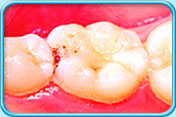

图中所见是蛀坏的牙齿补牙前的外貌。补牙前

图中所见是蛀坏的牙齿以复合树脂填补后的外貌。补牙后